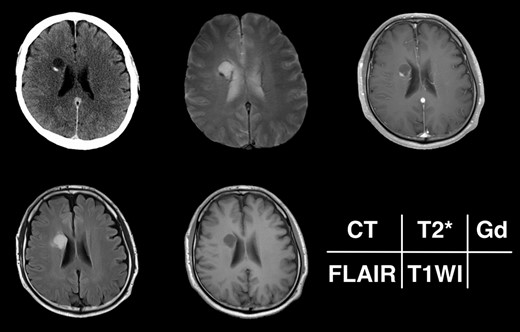

Given the absence of neurological symptoms, the patient was followed conservatively. After a follow-up period of 10 years, the lesion started to increase in size from 10 to 18 mm, accompanied by worsening of headaches. MRI revealed that the increased size of the lesion was attributable to an enlargement of the cystic component and the mural nodule (Fig. 1). A cystic mass with a gadolinium (Gd)-enhancing cyst wall and mural nodule were present. Signal intensity of the cystic component was high on T2-weighted imaging and fluid-attenuated inversion recovery (FLAIR) imaging. The cyst wall and nodule showed low signal intensity on T2*-weighted imaging (Fig. 2). Surgical removal was performed via a trans-cortical approach achieving gross total removal. The cystic component was covered with a transparent thin membrane containing clear yellow fluid, while the mural nodule comprised white, tough tumorous tissue. The lesion showed no invasion into the lateral ventricle. The postoperative course was uneventful, with no complications. No headache and no sign of recurrence have been seen, as of 13 months after surgery (Fig. 2).

Clinical course of the lesion on follow-up neuroimaging. The tumor increased in size during 10 years of follow-up. No recurrence has been seen as of 8 months postoperatively.

Radiological appearance of the lesion on CT and MRI. The lesion appears as a hypodense cyst with hyperdense nodules in the periventricular region on CT. Both the cystic wall and nodule show signal hypointensity on T2*-weighted images and Gd-enhancement on contrast-enhanced T1-weighted images. The cyst is hyperintense on FLAIR and hypointense on T1-weighted images.